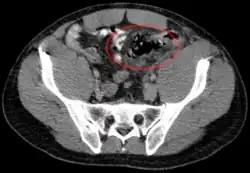

Die Diagnostik basiert auf der körperlichen Untersuchung und der Ultraschalldiagnostik. Bei Verdacht auf eine Darmperforation kann oftmals freie Luft in der Röntgenübersicht oder in der Computertomographie (deutlich sensitiver) nachgewiesen werden. Die Computertomographie kann darüber hinaus häufig die Ursache (z. B. Divertikulitis, Tumor des Dickdarms) identifizieren oder Komplikationen (z. B. Abszess, Fistel) aufdecken.